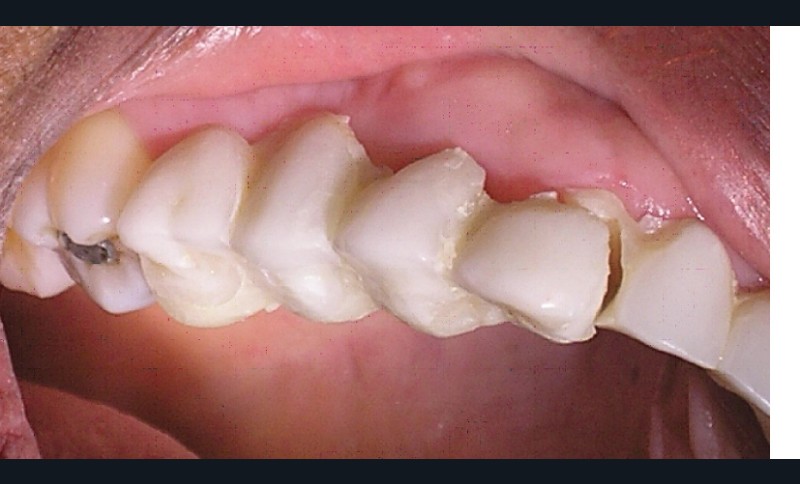

La patiente a été porteuse d’un bridge céramo-métallique de onze éléments au maxillaire pendant huit mois (fig. 1, 2), puis d’un bridge transitoire au maxillaire (fig. 3). Elle signale quelques rares épisodes de saignement probablement dus à l’irritation par la prothèse. Cette dernière se descelle couramment, créant ainsi un préjudice fonctionnel, esthétique et psychologique.

L’examen dentaire ne montre pas de mobilité dentaire. À l’arcade maxillaire, les dents 11, 14, 21, 22, 23 sont absentes. Les dents 13, 15, 24, 25 sont à l’état de racine (fig. 4). Nous notons des reconstitutions coronaires à l’amalgame sur les 26 et 16. À l’arcade mandibulaire, les dents 37, 36, 46, 47 sont absentes et une obturation coronaire à l’amalgame sur 38 est en place. Les bords libres du groupe incisivo-canin et les cuspides des prémolaires sont légèrement abrasés (fig. 5).

L’examen occlusal met en évidence une classe I d’Angle canine, un calage molaire insuffisant, une OIM instable, un plan d’occlusion perturbé et un guidage antérieur afonctionnel.